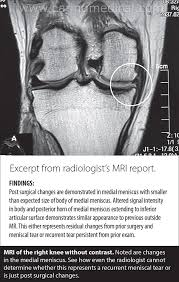

How Long Does An Mri Take Knee - Specifically for a knee mri, you will likely go in feet first and can generally expect the lower half of your body to be inside of the tube.. Leave time for filling out paper work and getting dressed for the scan as well. The dye helps the radiologist see certain areas more clearly. Magnetic resonance imaging (mri) is a technology often used to investigate the sources of knee problems. It can take longer if there is any motion, so try to stay still. Most knee mri scans take about 30 minutes,.

It is important to stay still during this period. If your knee pain is not getting better on its. Mri results are usually available to a doctor within one to two days, reports webmd. These orientations are then translated into images we can use for diagnosis. Why does it take so long to get an mri approved? The scan is painless and can take anywhere from 15 to 90 minutes depending upon what the mri is scanning. Thank you for posting on this forum, it helps a lot. Ultimately, the answer to this question is that it depends.

Leave time for filling out paper work and getting dressed for the scan as well. The knee mri can take 30 minutes to an hour. Slices must be sufficient to cover the whole lower leg anterior to posterior. In other cases, it might take a few days. Most knee mri scans take about 30 minutes,. Meet scott, a technologist for michigan residence imaging. Diagnostic radiology 42 years experience. The images can be stored on a computer or printed on film. A patient with knee pain may undergo an mri to enable a doctor to make a diagnosis. How long does it take to get mri results? In some situations, you may get your mri scan results back in as little as a few hours. Specifically for a knee mri, you will likely go in feet first and can generally expect the lower half of your body to be inside of the tube. The test most often lasts 30 to 60 minutes, but may take longer.

A patient with knee pain may undergo an mri to enable a doctor to make a diagnosis. The test usually takes 30 to 60 minutes but can take as long as 2 hours. The scan is painless and can take anywhere from 15 to 90 minutes depending upon what the mri is scanning. 4k views answered >2 years ago. The test most often lasts 30 to 60 minutes, but may take longer.